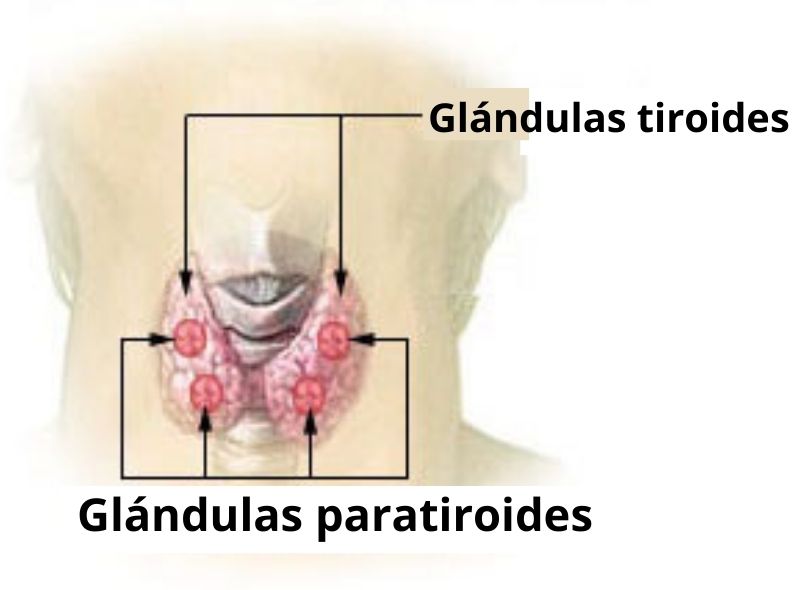

Estas glándulas se encargan principalmente de la liberación de hormonas, las cuales son distribuidas hacia los distintos órganos “diana”. Las glándulas endocrinas más importantes del cuerpo son las glándulas suprarrenales o adrenales, la hipófisis, la tiroides, la paratiroides y la glándula pineal, los ovarios, la placenta y los testículos.

– La tiroides se encuentra en el cuello y participa de la secreción de la hormona tiroxina, triyodotironina y calcitonina, que también influyen sobre el metabolismo.